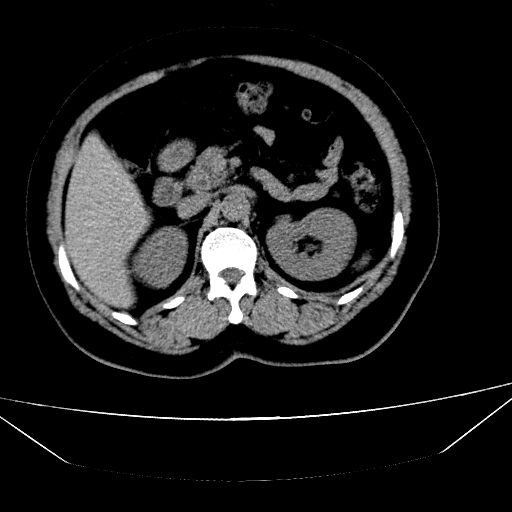

CT50057:肾结石还是钙化

病人,女,左腹部隐痛2年,彩超左肾结石。

左肾结石

多位钙化。

考虑钙化。